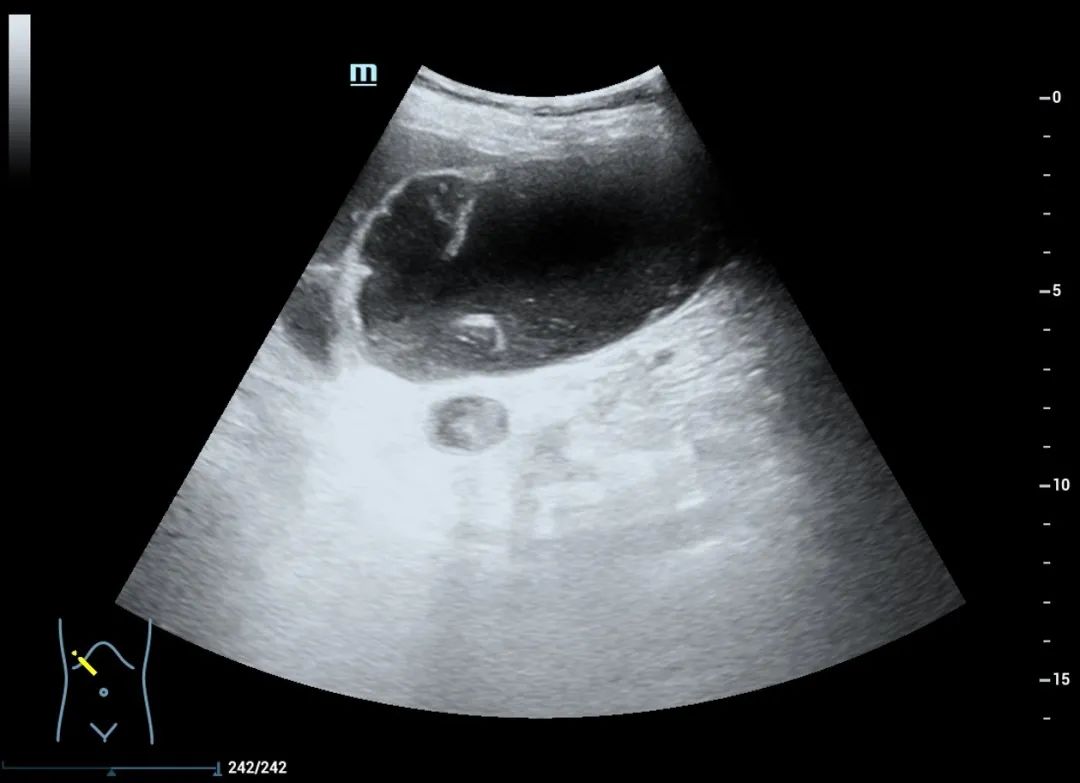

肿大的胆囊张力很高,胆囊壁增厚,囊内胆汁透声不佳,有结石,有胆泥沉积物,同时肝内外扩张的胆管均提示患者的胆囊等不起了,一旦穿孔进展为腹膜炎,以患者的身体条件,几乎难以扛过。

在超声介入医生准确的评估、完善的路径规划和娴熟的操作下,局麻——进针——减压——导丝——扩皮——置管——固定,一步步操作,按部就班、娴熟流畅、有条不紊的进行着,全程监控,避开血管,一次成功,安全顺利的完成了置管,即刻引流出草绿色胆汁50ml,经评估置管通畅,患者胆囊的危象得到了缓解,有效控制了胆囊肿大及胆管扩张带来的危险,给临床心梗对症处理及抗炎治疗赢得了时间。